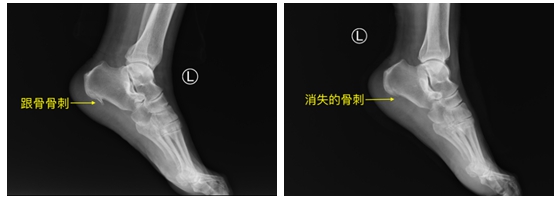

家住常德的刘阿姨,因左足跟反复疼痛10年,行走困难,特别在长时间行走后,疼痛尤为明显,有针刺样疼痛感,严重影响日常生活。经多种治疗无明显疗效,刘阿姨前来骨科常德病区门诊就诊。骨科王拓副主任医师详细询问病史、体格检查后,结合影像学检查诊断为:1.左足跟痛症 2.左足跟骨骨刺 3.左足跖底筋膜炎,通俗的说就是刘阿姨脚底板长了一个“长长的骨刺”。

与患者及家属详细沟通并取得同意后,骨科关节组团队决定运用关节镜微创行左足跟骨骨刺切除+跖底筋膜松解手术。本次手术由王拓副主任医师主刀,唐初主治医师一助,术中只需在左足内侧作两个0.5cm切口,运用关节镜技术直达病灶,在关节镜的监视下完全切除骨刺并精准松解病变的跖底筋膜,手术时间不到1小时。术后第二天刘阿姨即可下地行走,目前刘阿姨伤口已拆线,跟痛症状完全消失,行走已无疼痛感,已恢复日常生活。

据王拓副主任医师介绍,跟痛症常见于中老年群体,约每10人中就会有1人在一生之中经历足跟痛,跟痛症患者占据了骨科医生门诊的1%,目前跟痛症病因以跟骨骨刺及跖底筋膜炎为主,约50%的跟痛症患者伴有跟骨骨刺,常见症状以足跟疼痛为主,行走时尤为明显,不能长时间行走,有时伴有针刺样疼痛。大部分跟痛症患者通过口服药物、改变生活方式、局部注射类固醇激素、PRP(富血小板血浆)、理疗等保守治疗,症状可以缓解,仍有10%的跟痛症患者持续保守治疗效果不佳,进一步发展为顽固性跟痛症,对于伴有跟骨骨刺的顽固性跟痛症,需要切除骨刺并松解跖底筋膜,才能达到缓解症状的目的,以往切除跟骨骨刺需要开刀,创伤大,恢复慢,跖底筋膜松解也不能很精准,且大部分患者难以接受开刀治疗,随着关节镜技术的不断发展,关节镜微创不仅能够实现全方位切除骨刺,还能精准进行跖底筋膜松解,达到充分缓解症状的目的,创伤小,恢复快。